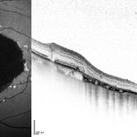

Fundus autofluorescence and SD-OCT of a 70-year-old woman with geographic atrophy sec. to Central areolar choroidal dystrophy